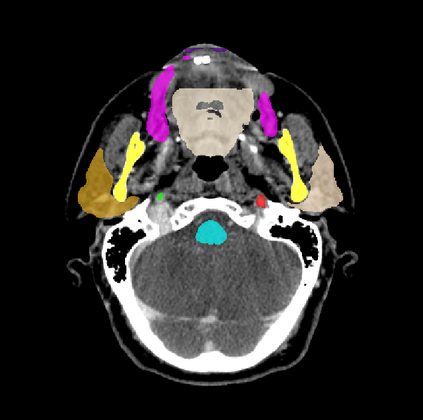

Organ at risk (OAR) segmentation is a critical process in radiotherapy treatment planning such as head and neck tumors. Nevertheless, in clinical practice, radiation oncologists predominantly perform OAR segmentations manually on CT scans. This manual process is highly time-consuming and expensive, limiting the number of patients who can receive timely radiotherapy. Additionally, CT scans offer lower soft-tissue contrast compared to MRI. Despite MRI providing superior soft-tissue visualization, its time-consuming nature makes it infeasible for real-time treatment planning. To address these challenges, we propose a method called SegReg, which utilizes Elastic Symmetric Normalization for registering MRI to perform OAR segmentation. SegReg outperforms the CT-only baseline by 16.78% in mDSC and 18.77% in mIoU, showing that it effectively combines the geometric accuracy of CT with the superior soft-tissue contrast of MRI, making accurate automated OAR segmentation for clinical practice become possible. See project website https://steve-zeyu-zhang.github.io/SegReg